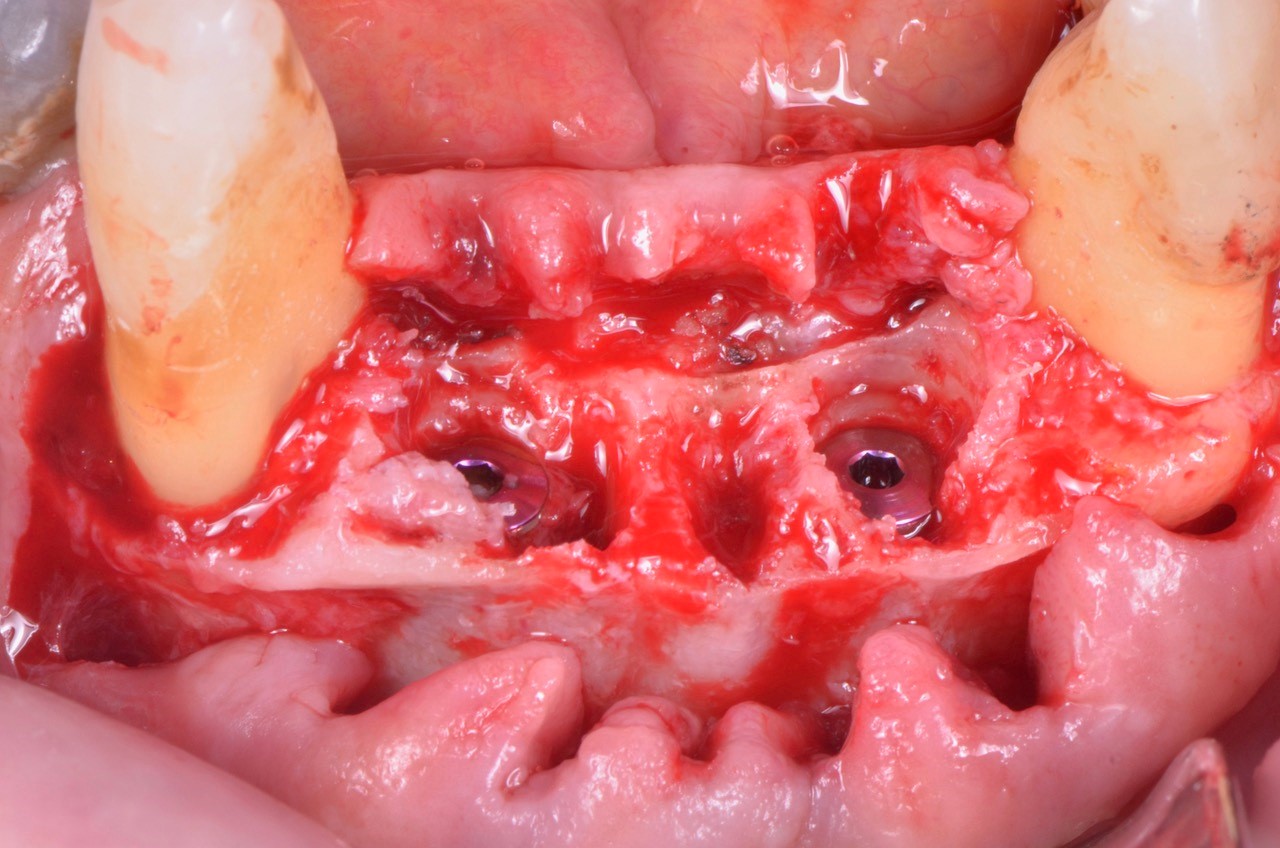

Posizionamento sub crestale di due V3

Foto: Posizionamento subcrestale di due impianti MIS V3

Le foto di questo articolo sono state gentilmente concesse dal Dott. Federico Rivara.